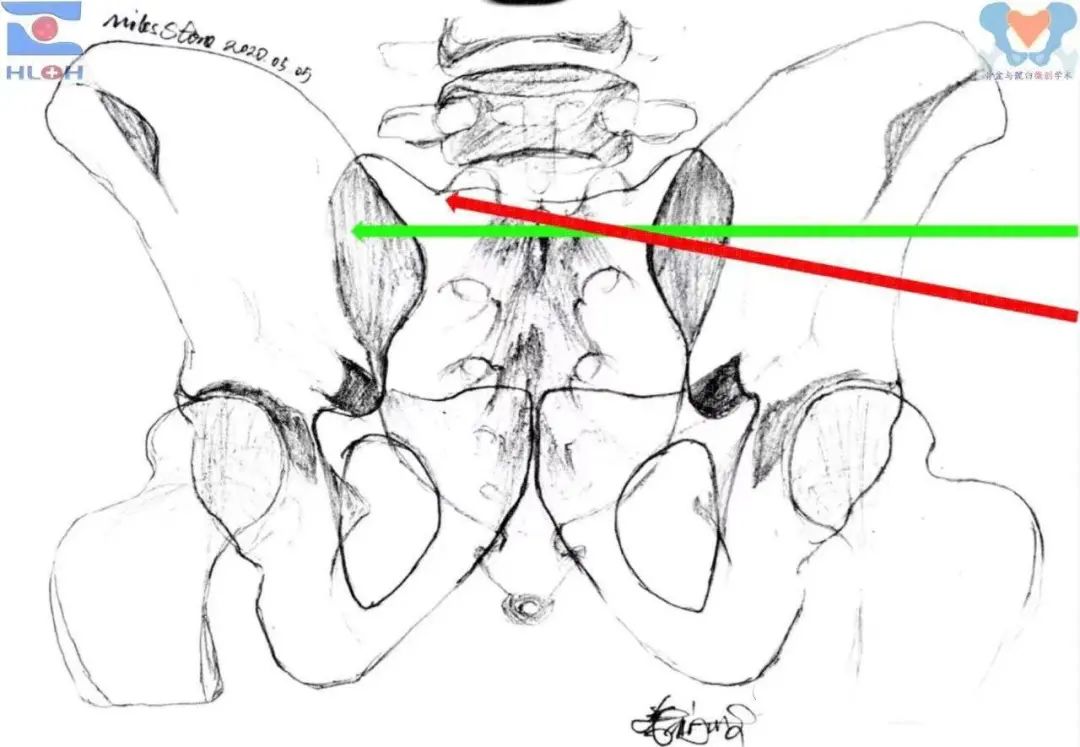

骶髂螺钉导针指向调整的传统方法是,在骨盆出口位像上调整导针,使其行进并就位于同侧骶1骶前孔和骶骨翼斜坡之间,同时在骨盆入口位像上,使其行进并就位于骶1椎体及同侧侧块前缘与骶管之间。这种方法由手术技术创立伊始延续至今,虽安全可行,但效率低下,放射线暴露量大,骨盆出口位和入口位像之间的非正交关系是其症结,常常导致一像上的良好指向在调整另一像上不良指向过程中出现丢失而反复调整,甚至丢失已建立好的进针点的情况,在置入骶1斜向(拉力)骶髂螺钉过程中尤为普遍。

传统的导针指向调整方法(标准骨盆出口位像)绿箭:骶1平向骶髂螺钉、红箭:骶1斜向骶髂螺钉

传统的导针指向调整方法(标准骨盆入口位像)

绿箭:骶1平向骶髂螺钉、红箭:骶1斜向骶髂螺钉